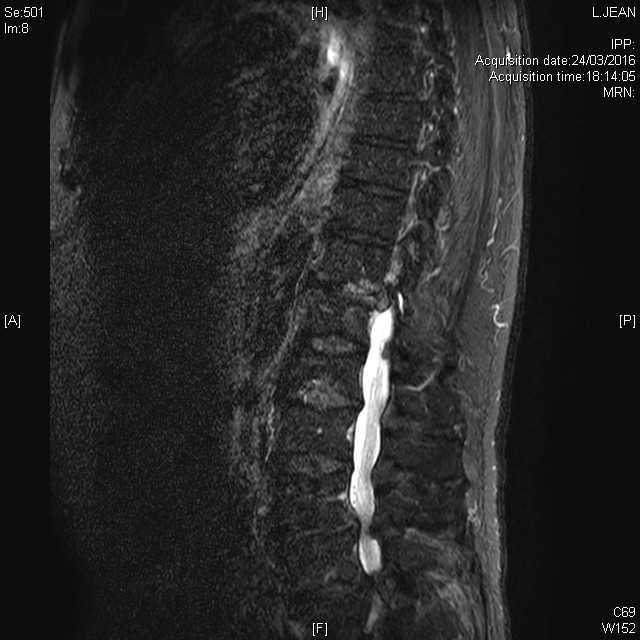

Multiples lésions vertébrales rachidiennes avec compression médullaire et épidurite à l'étage T5, dans le cadre d'un cancer pulmonaire, en séquence T2 STIR

Plasmocytome solitaire du rachis dorsal découvert dans le cadre du bilan d'une fracture vertébrale dorsale spontanée

Tableau clinique de compression médullaire en rapport avec une hernie discale thoracique exclue